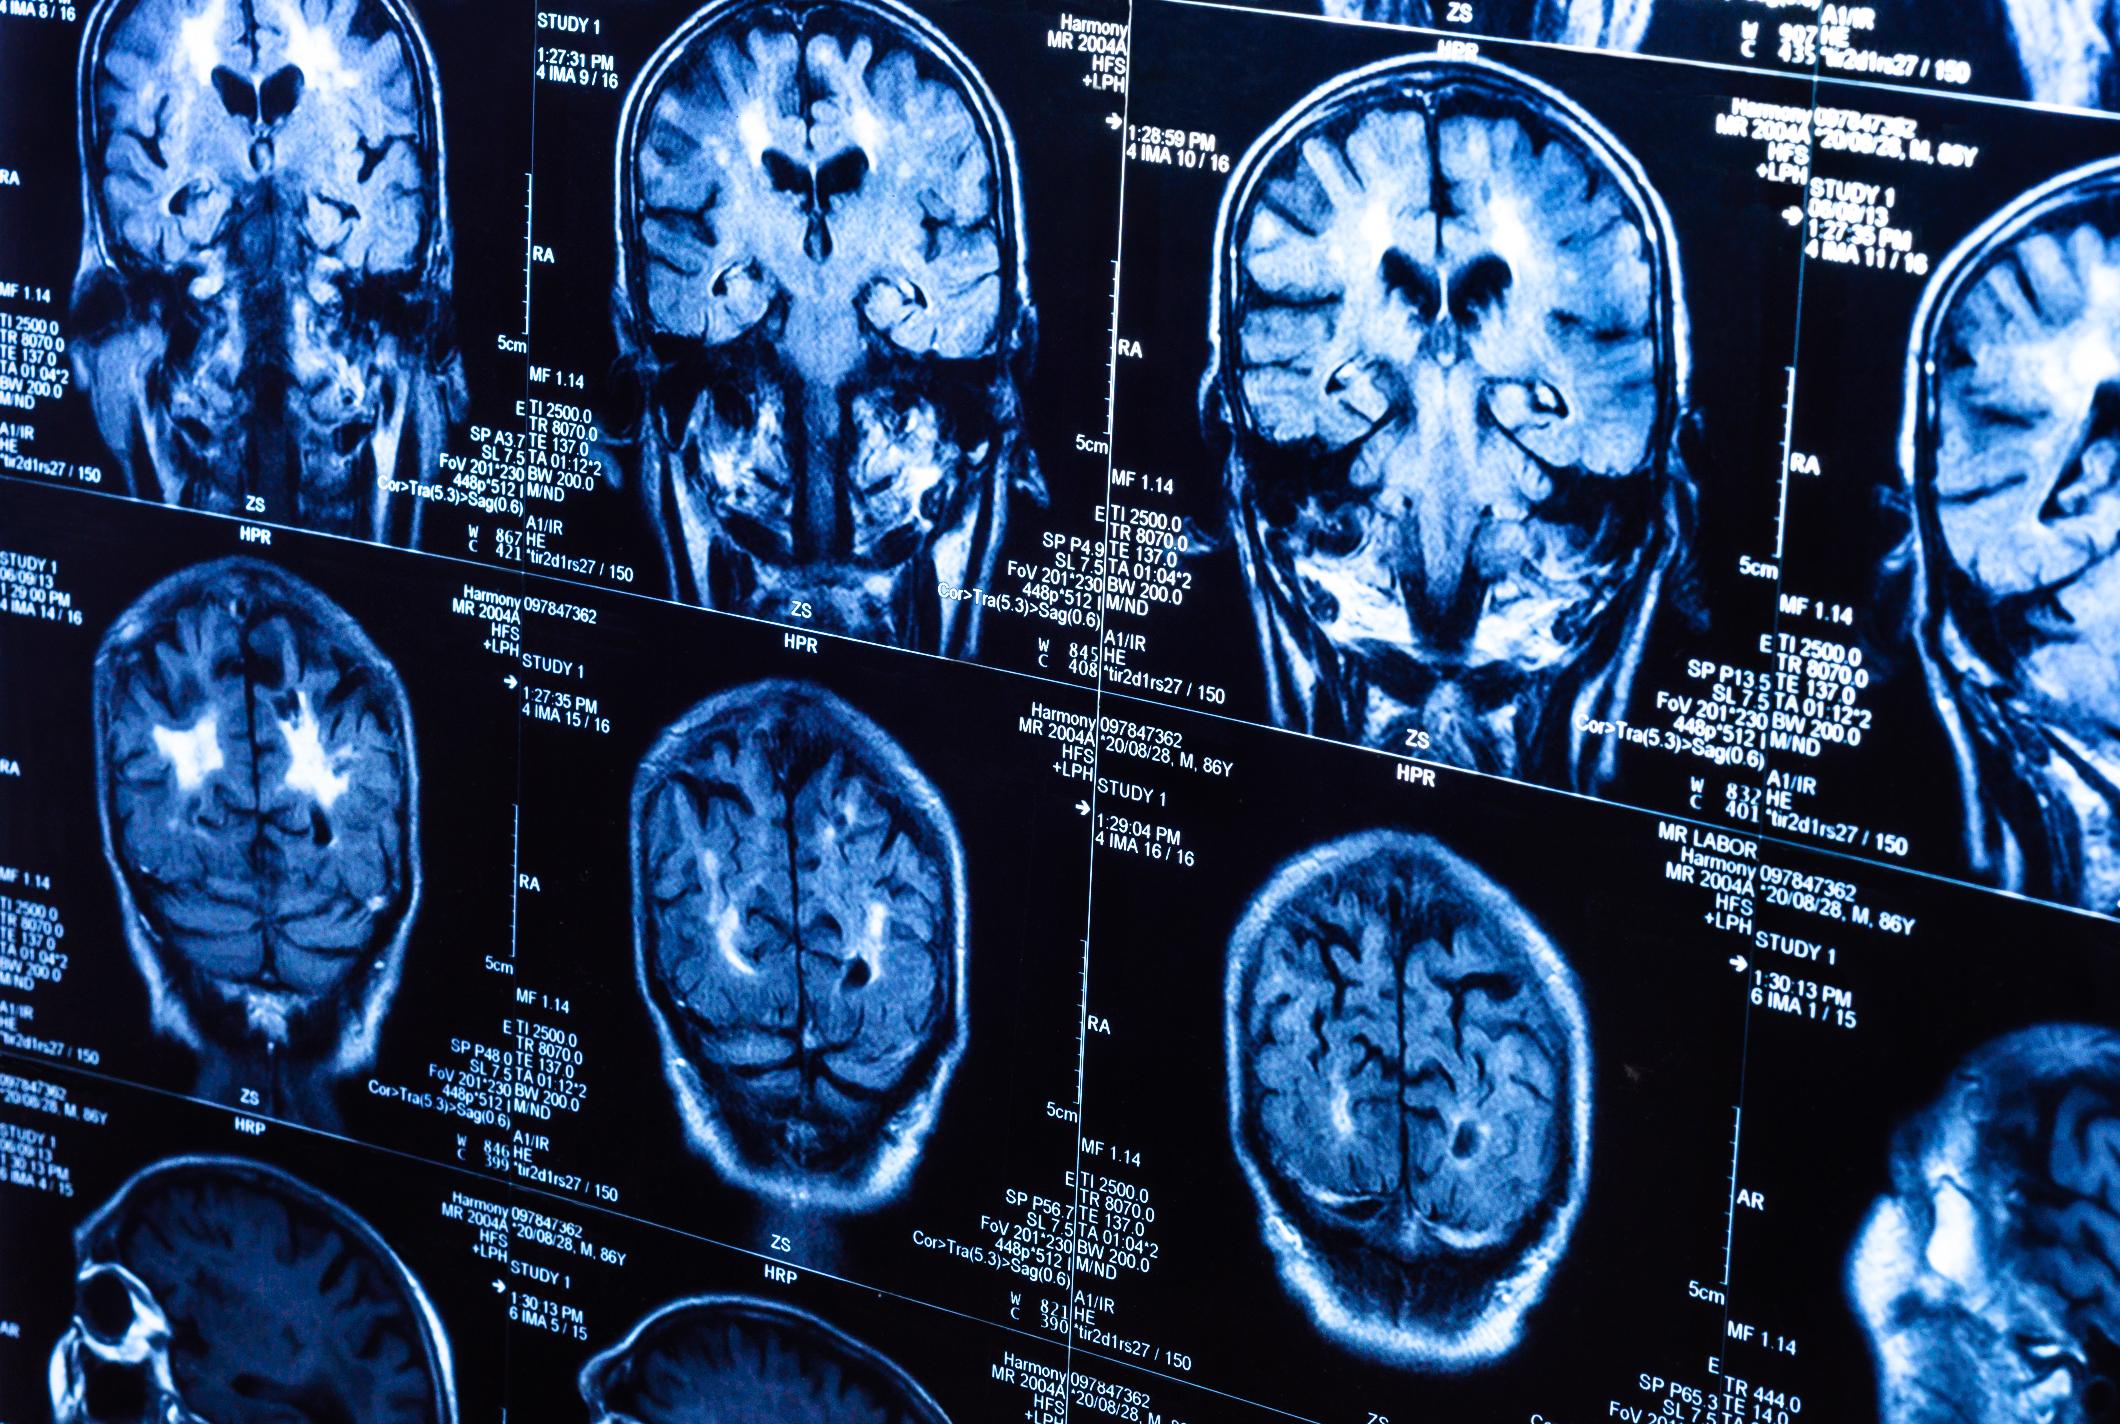

Mobil cihazlar beyin xərçənginə yol açırmı?

Uzun sürən tədqiqatlar sonrası alimlər müasir dövrün vacib

suallarından birinə tam dəqiq cavab veriblər. Mobil telefonlar beyin xərçənginə

gətirib çıxardırmı? Mobil telefonların zərərləri haqqında söz söhbətlər uzun

illərdirki var. Lakin bir çox tədqiqatlar bu suala tam dəqiq cavab verə

bilmirdi. İndi isə Sidney Universitetinin alimləri mobil telefonlar ilə beyin xərçəngi

kimi ölümcül xəstəliklər arasındakı əlaqənin olub olmaması sualına demək olar

ki, aydınlıq gətiriblər. Alimlər 30 illik məlumatları müşahidə edərək bildiriblər

ki, mobil telefonlar ilə beyin xərçəngi xəstəliyi arasında heç bir əlaqə

yoxdur. Avstraliyada ilk mobil telefonlar 1987-ci ildə yayılmışdı. O vaxt mobil

cihazlardan çox az adam istifadə etsə də indi 90% avstraliyalı şəxs mobil

cihazlardan istifadə edir. Lakin mobil telefonların sayının artması beyin xərçəngi

göstəricilərinə heç bir təsir etmədi. Beyin xərçəngi xəstəliyinin kəskin şəkildə

artması məhz 80-ci illərə təsadüf edir. Həmin illərdə isə mobil telefonlardan həddən

artıq az sayda insan istifadə edirdi. Buna baxmayaraq elə tədqiqatlar da var

ki, sözügedən müşahidələrin tam əksini söyləyir.